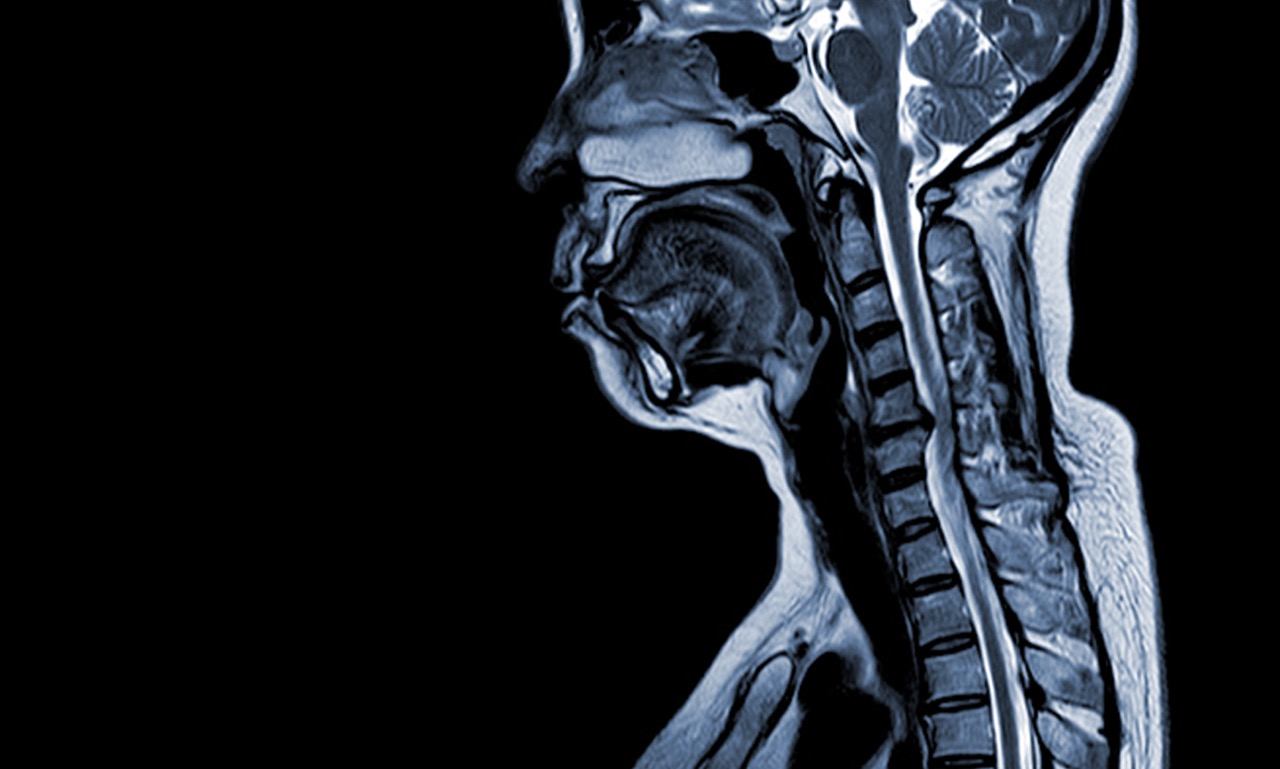

When Should I Get a Cervical MRI? Your neck throbs constantly, making it painful to look over your shoulder while